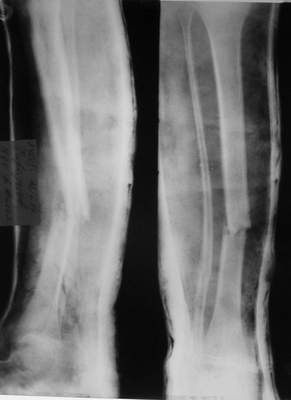

Первичные

|

Вытяжение

Фиксация

в гипсе

Промежуточный